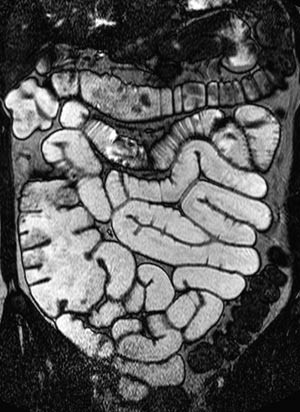

MR av tynntarm med sonde

En viktig forutsetning for radiologisk fremstilling av tynntarmen er at tarmslyngene er utspilt. Hvis tynntarmen har falt sammen, kan patologiske tilstander overses. Én MR-metode innebærer nedleggelse av sonde til tynntarmen og installasjon av væske i denne (1) – (6). Væsken vil vanligvis være tilsatt et stoff som hindrer absorpsjon. Undersøkelsen starter med at pasienten får lagt ned en sonde til proksimale tynntarm på et gjennomlysningslaboratorium. Sonden blir lagt forbi Treitz’ ligament. Den har en ballong distalt som hindrer refluks til ventrikkelen. Deretter fortsetter undersøkelsen på MR-laboratoriet. Pasienten ligger i bukleie i magneten. Sonden kobles til en pose med væske. Væskeinfusjonen starter ved hjelp av manuell installasjon og overvåkes med MR-fluoroskopi (fig 1). Når høyre colonhalvdel er godt væskefylt, stoppes væskeinstallasjonen og man starter de øvrige sekvensene.

Bruk av sonde gir god utvidelse av både jejunum og ileum (fig 2). Duodenum blir vanligvis ikke fylt med væske fordi sondeballongen hindrer refluks. Av og til vil heller ikke proksimale jejunum bli fremstilt fordi sonden vandrer i distal retning. Den største ulempen med metoden er likevel nedleggelsen av sonden. Pasientene opplever dette som ubehagelig, og prosedyren innebærer fortsatt noe strålebelastning. Det er derfor stor interesse for MR-undersøkelse av tynntarm med oral kontrast.